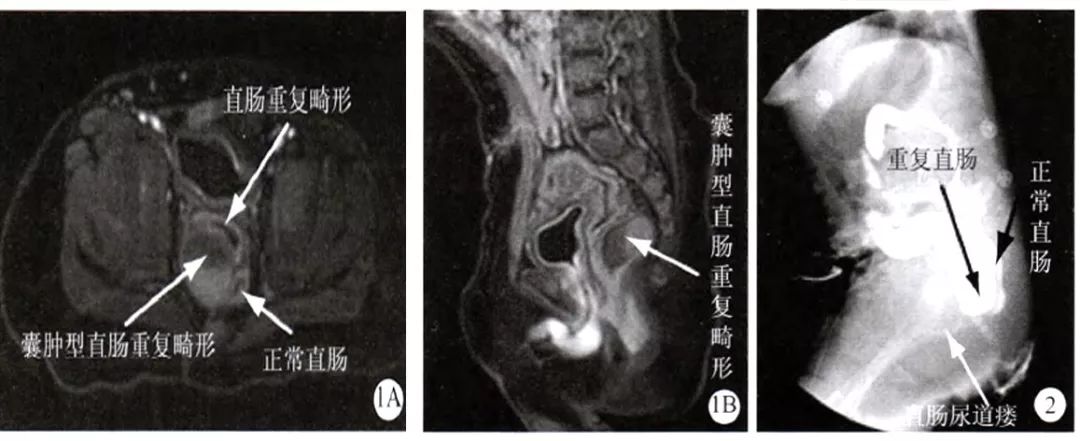

图1 MRI检查示盆底为三腔结构,在重复直肠和正常直肠间存在囊肿型重复畸形,1A横断位;1B矢状位

图2造影可以清晰显示重复直肠和正常直肠被推挤压迫,重复直肠与尿道形成瘘管